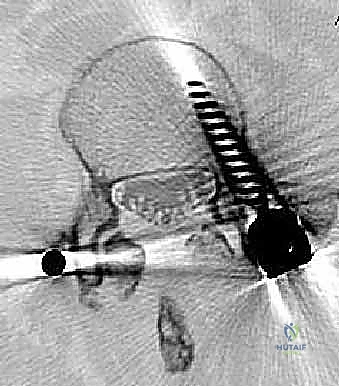

عملية دمج الفقرات (Spinal Fusion) هي إجراء جراحي يهدف إلى ربط فقرتين أو أكثر بشكل دائم، مما يزيل الحركة غير الطبيعية والمؤلمة بينهما، ويعيد الاستقرار الميكانيكي إلى العمود الفقري. في حالتنا هذه، يتم التركيز بشكل خاص على المنطقة الصدرية القطنية (Thoracolumbar Junction)، وهي المنطقة الانتقالية الحرجة التي تربط الجزء العلوي من الظهر (القفص الصدري الصلب) بالجزء السفلي (المنطقة القطنية المتحركة). يتم التثبيت باستخدام أدوات طبية معدنية متطورة (Instrumentation) مثل المسامير السويقية (Pedicle Screws) والقضبان المصنوعة من التيتانيوم.

السويقات الفقارية (Pedicles): دعامة التثبيت الأساسية والمحورية

تعتبر السويقة الفقارية (Pedicle) جسرًا عظميًا أسطوانيًا يربط الأجزاء الخلفية للفقرة (القوس الفقري) بالجسم الفقري الأمامي الضخم. في جراحة دمج الفقرات الحديثة، تعتبر السويقة نقطة التثبيت الرئيسية والأقوى للمسامير المستخدمة في العملية (Pedicle Screws). يختلف شكل وحجم وزاوية السويقات بشكل كبير على طول العمود الفقري، وفهم هذه الفروق الدقيقة أمر بالغ الأهمية للجراح لضمان وضع المسامير بأمان تام وفعالية قصوى دون الإضرار بالأعصاب أو الأوعية الدموية.

- تبني أحدث التقنيات التكنولوجية: يستخدم د. هطيف تقنيات الجراحة الميكروسكوبية الدقيقة (Microsurgery)، ومناظير المفاصل بدقة 4K، وأنظمة الملاحة الجراحية لضمان وضع المسامير بدقة متناهية (Sub-millimeter accuracy) وتجنب أي إصابة للأعصاب.